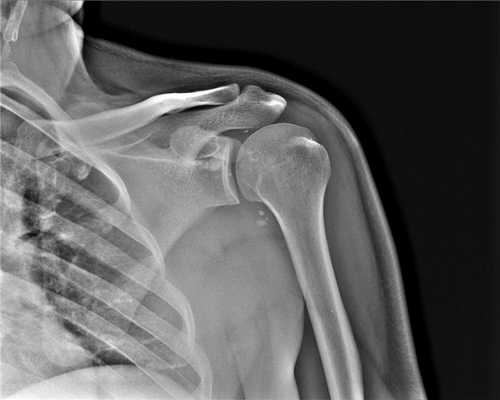

(Слева) На боковой рентгенограмме определяется задний вывих предплечья, в том числе локтевого отростка и головки лучевой кости. Большой отломок головки лучевой кости расположен кпереди от головки мыщелка плечевой кости.

(Справа) На передне-задней рентгенограмме определяется латеральное направление типичного вывиха. Видна вывихнутая головка лучевой кости с большим дефектом, вывихнутая локтевая костью и отломок перелома головки лучевой кости. Примерно 90% вывихов предплечья являются заднебоковыми по направлению. (Слева) На боковой рентгенограмме у подростка 11 лет определяется задний вывих локтевого и лучеголовчатого суставов. Отломки находятся в суставе.

2. Рентгенография при вывихе предплечья:

• Полная потеря сочленения между блоком и локтевой костью:

о Обычно смещение локтевой кости кзади

• Сопутствующий вывих головки лучевой кости

• Сопутствующие переломы